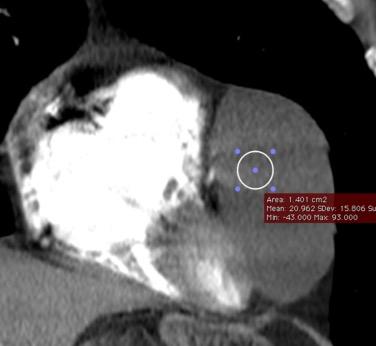

123 .MASA MEDIASTÍNICA CON ALTA DENSIDAD I INTRÍNSECA

Mod. de Glazer HS et al. High-attenuation mediastinal masses on unenhanced CT. Radiology 1991